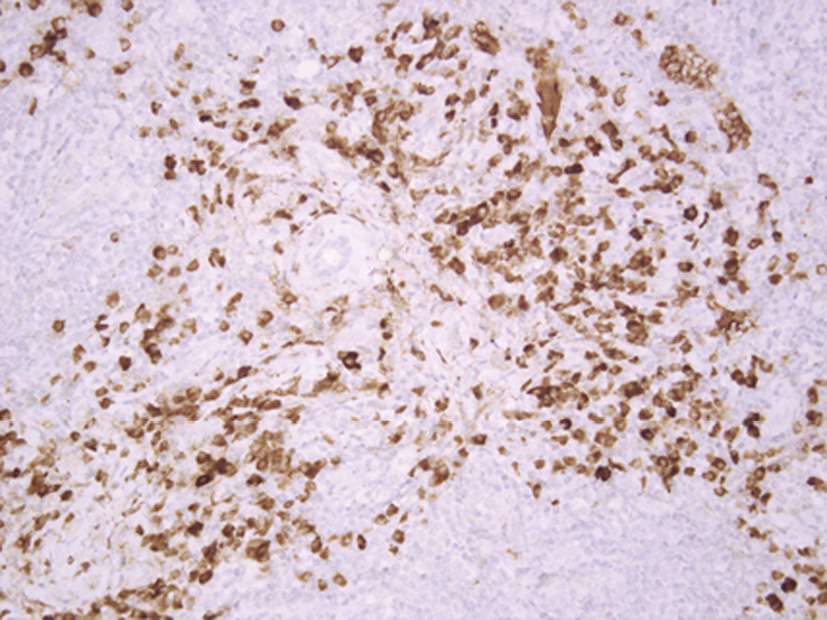

При гистологическом исследовании выявлены фрагменты фиброзной ткани со структурами слезной железы, многочисленными лимфоидными фолликулами с широкими центрами размножения; присутствовали пласты зрелых плазматических клеток, расположенных парафолликулярно, перидуктально, часть из них – интрафолликулярно, с примесью эозинофильных гранулоцитов (рис. 3, 4).

Рис. 4. Участки зрелоклеточной плазмоклеточной инфильтрации с примесью эозинофильных гранулоцитов.

Окраска гематоксилином и эозином (ув. ×200).

Рис. 4. Участки зрелоклеточной плазмоклеточной инфильтрации с примесью эозинофильных гранулоцитов. Окраска гематоксилином и эозином (ув. ×200). Доступен на цветной вклейке и в сети Интернет: https://doi.org/10.14341/probl10223-4023 |

|